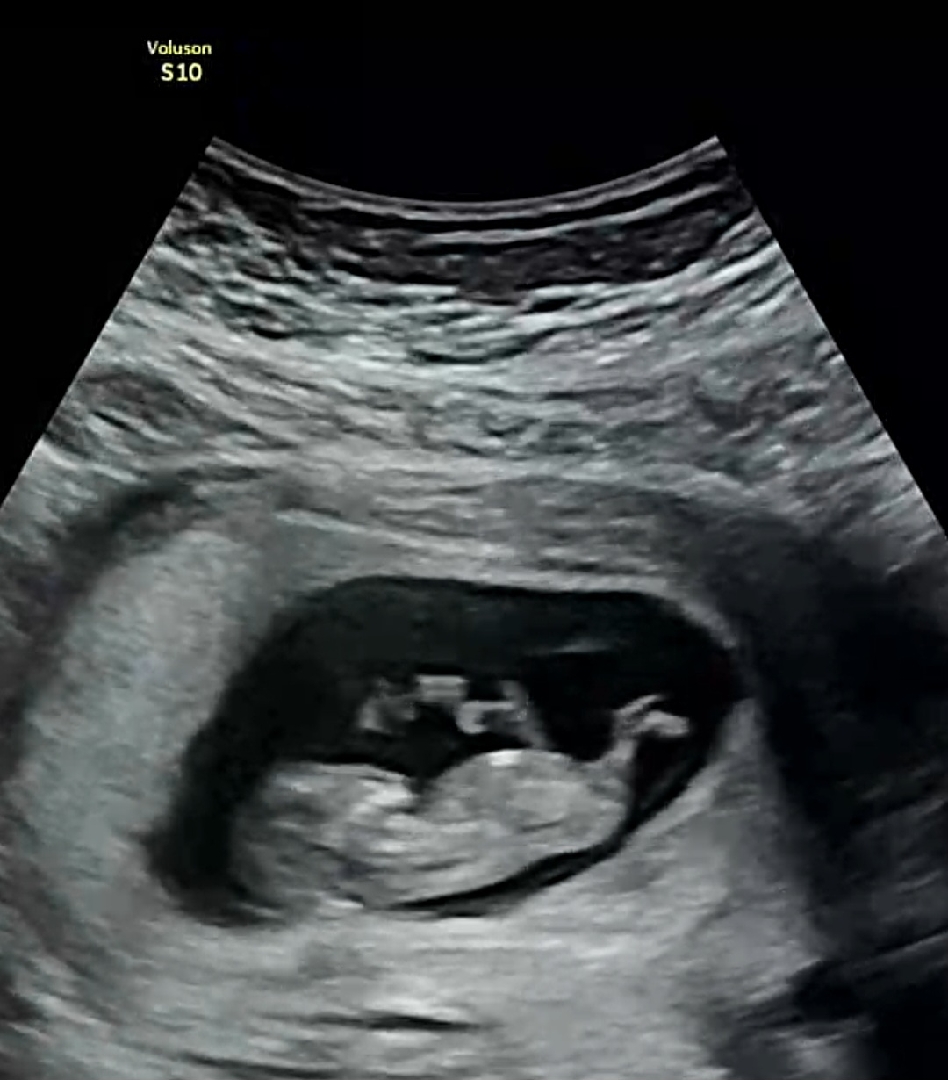

11주초에 찍은거긴한데.. 각도로 구분할수잇을까용....? 날이갈수록 궁금해지네용 ㅠㅜ 지금은.12주가 다되어가는데 병원 재내원까지 시간이 좀 멀어서ㅜㅜ헿...